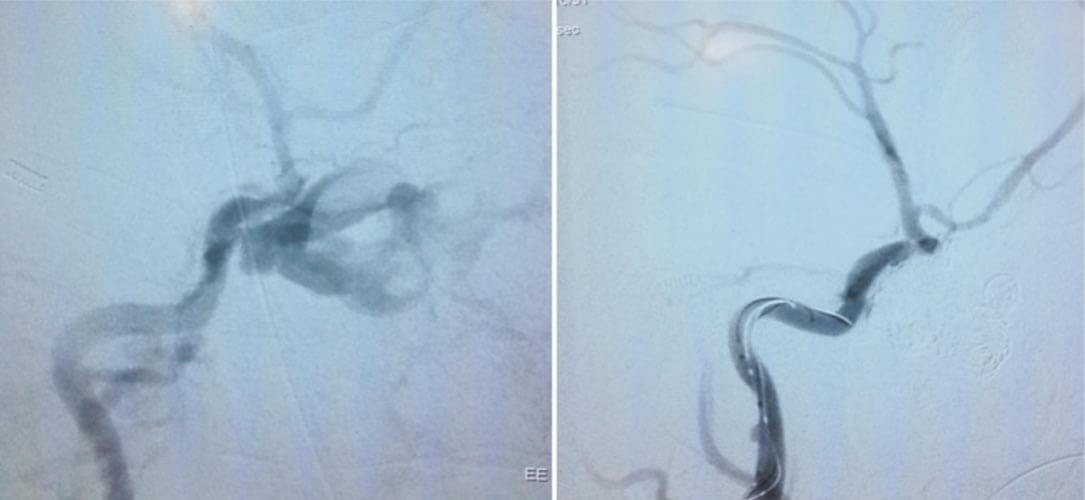

Ineffective recanalizations, insignificant functional outcomes, reperfusion haemorrhages, intraprocedural device induced complications, thrombolytic associated cerebral hemorrhages were the main factors for lack of impetus in active stroke interventions that has led to scepticism associated with the modality among neurologists in stroke treatment. However, the innovative use of of clot retrieval stents also called as stent retrievers (Eg- Solitaire device, Revive device) in ischemic stroke has been the major breakthrough in endovascular intervention for stroke. With the advent of stentrievers, there is a paradigm shift in endovascular intervention from thrombolysis to mechanical thrombectomy.

Various randomised clinical trials which have been published in early 2015 in NEJM (MR- CLEAN, ESCAPE, EXTEND-1A, SWIFT PRIME, REVASCAT) has given these stentrievers edge over the conventional medical management in selected cases. With the available advanced imaging techniques, cath lab technology and advanced stentrievers, endovascular intervention has established its role in clinical management of acute ischemic stroke.